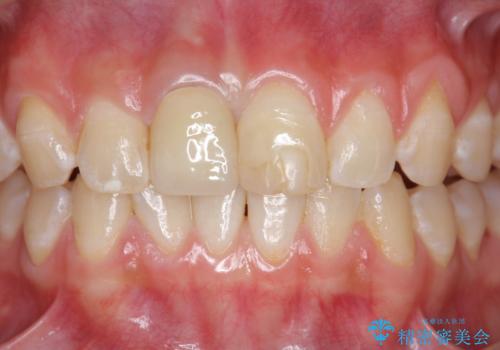

前歯をきれいにしたい ジルコニアクラウンによる審美治療

- 前歯の見た目の改善を求めて来院されました。

ジルコニアクラウンによる審美性の改善を計画します。

失活歯のため捻転を改善し、根管治療は特に希望されなかったのでそのままとしました。

今回失活歯であったため捻転を取り反対側の前歯に揃えて補綴を行うことができました。